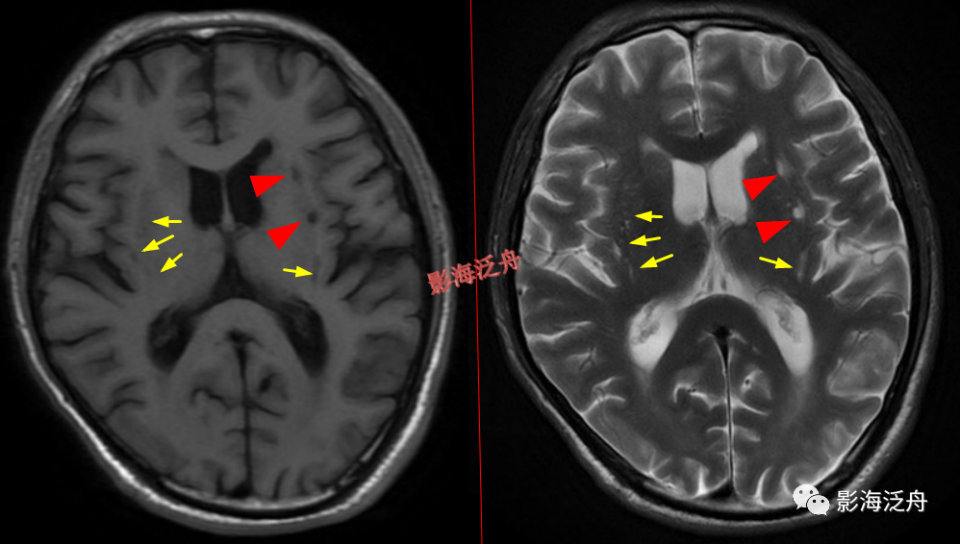

II型-大脑半球型:扩大VR腔隙呈对称性广泛分布于双侧半卵圆中心及皮层下白质区域(黄箭),少位于扣带回旁(白箭),部分呈类圆形(红箭头),部分呈裂隙样/线样(蓝箭头),注意绿箭头所指的VR腔隙边缘可见Flair高信号影,这种高信号可能是局部液体少量渗漏造成的。

III型-中脑型:左侧大脑脚可见细条状T2WI高信号影(红箭),Flair序列上未见异常信号(黄圈为中脑左侧部),随访病灶大小及信号均无明显变化。III型VR腔隙扩大是最少见的,多数审核老师喜欢不分青红皂白直接诊断为腔梗灶,毕竟是脑干区域,报的过一点也无妨。